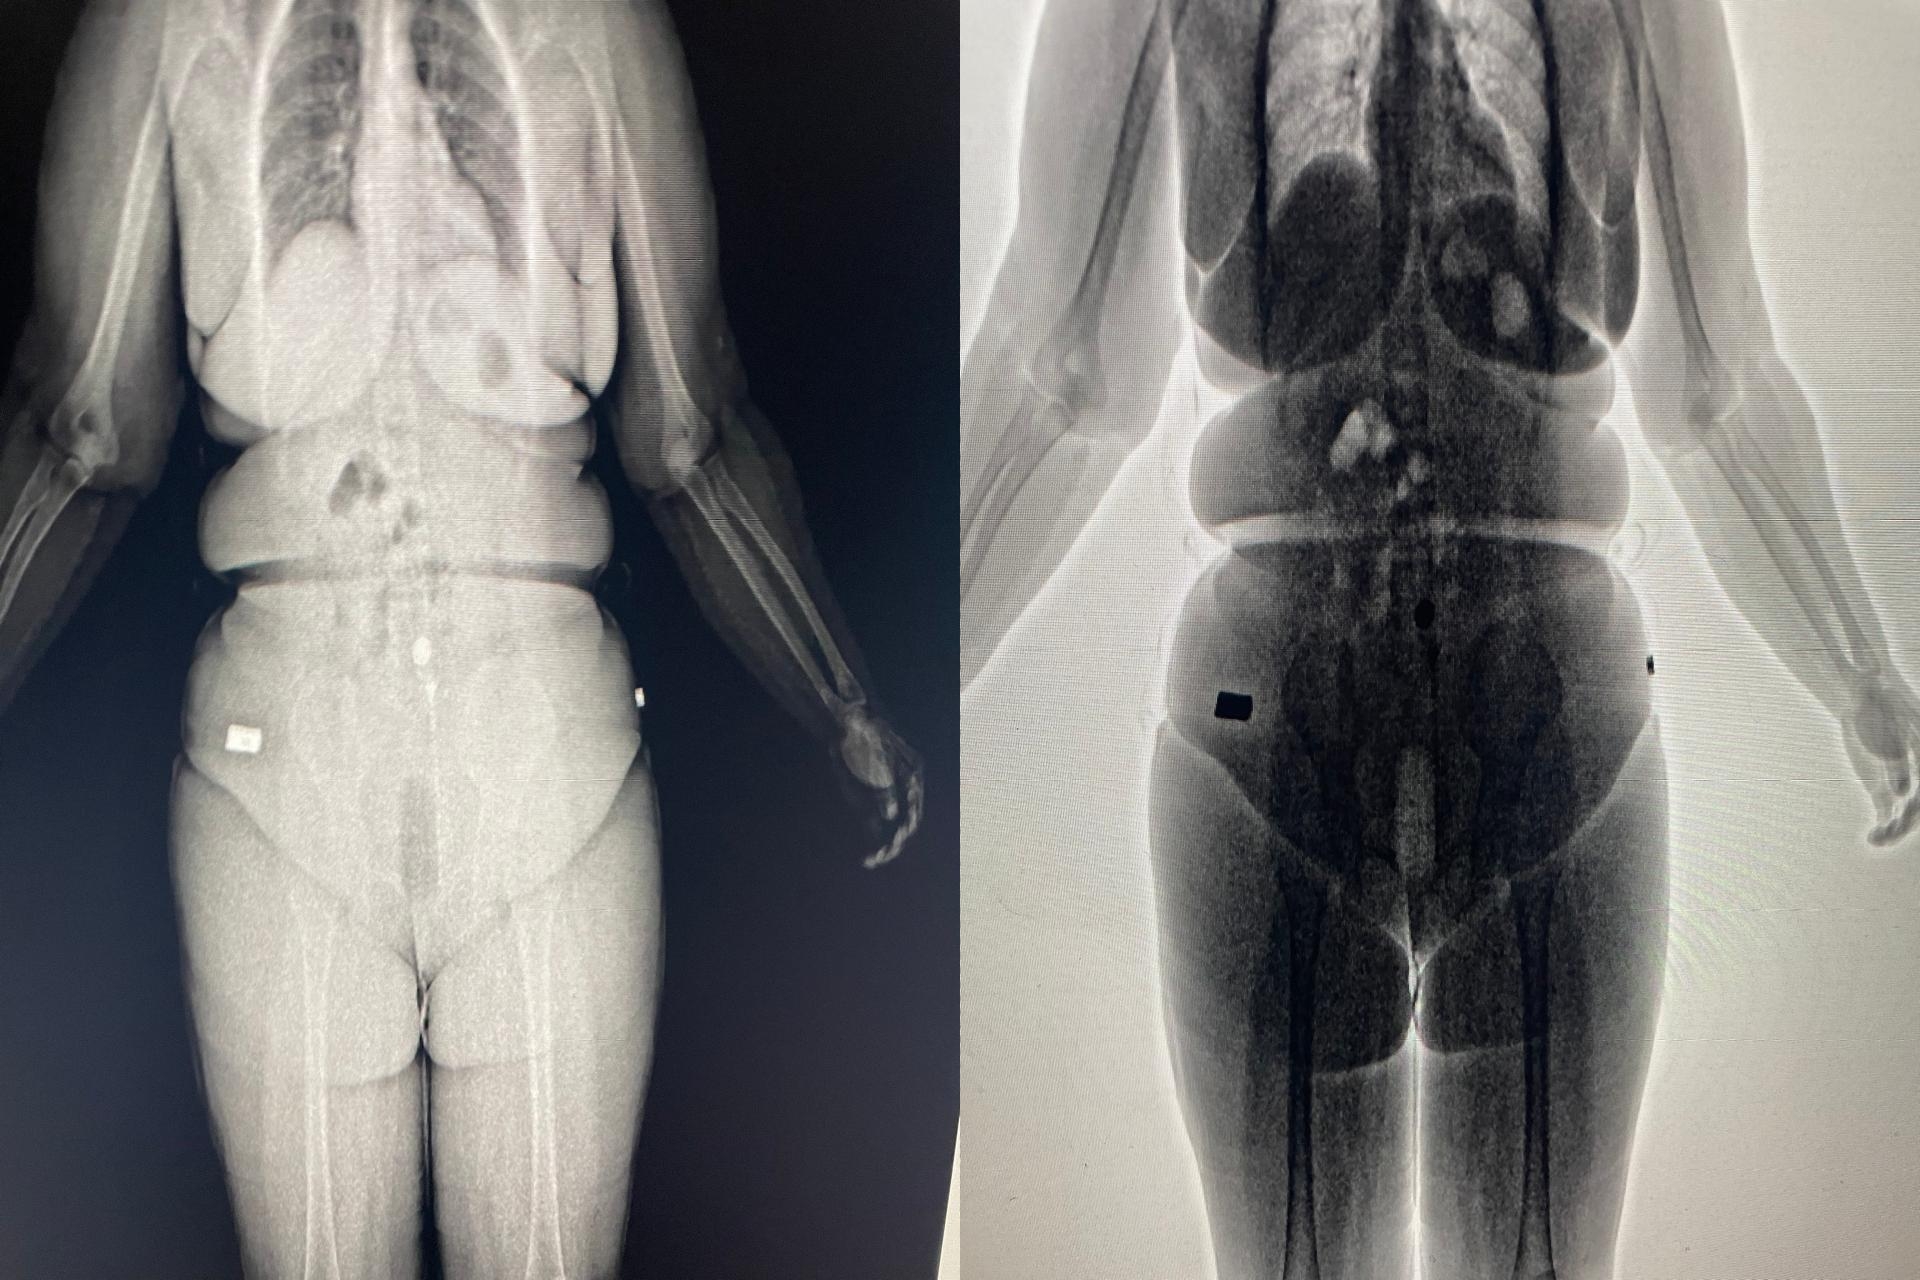

(Foto: reprodução)